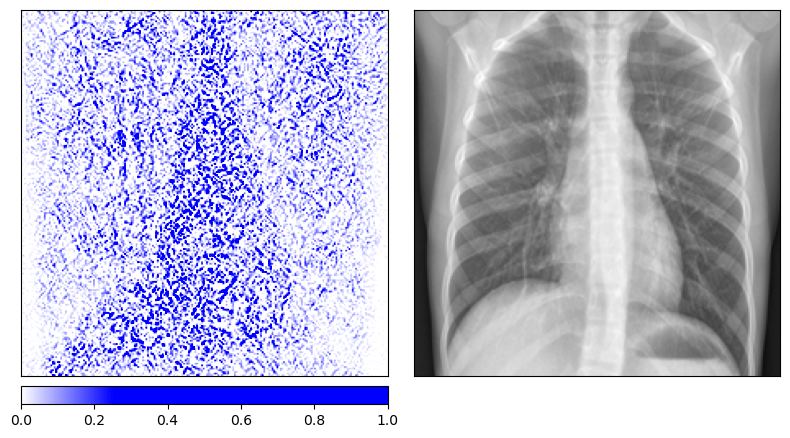

We retrain the same ResNet-50 architecture on the pneumonia dataset with randomly permuted training labels for 200 epochs. As expected, the model’s balanced accuracy drops to 0.52, essentially random chance. The Integrated Gradients maps for the permuted-label model look qualitatively different from those of the properly trained model. The attributions for healthy and diseased patients become indistinguishable, with both showing a similar scattered pattern that outlines anatomical structures without any class-specific focus.

Integrated Gradients on truly diseased patients (permuted-label model)

|

Both methods pass the data randomization test. The attribution maps change substantially when the model is trained on meaningless labels, confirming that they reflect the model’s learned decision function rather than low-level image properties. This is an important validation step that is often overlooked when deploying explainability tools in practice.